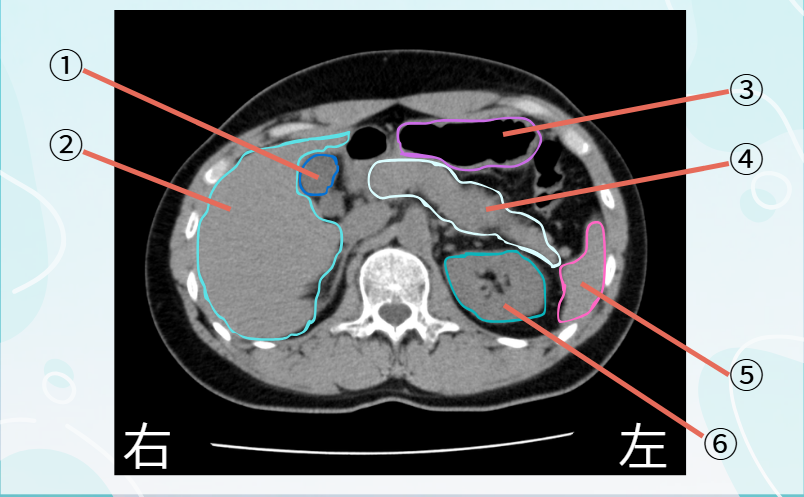

CT画像 クイズ

CT

画像クイズ